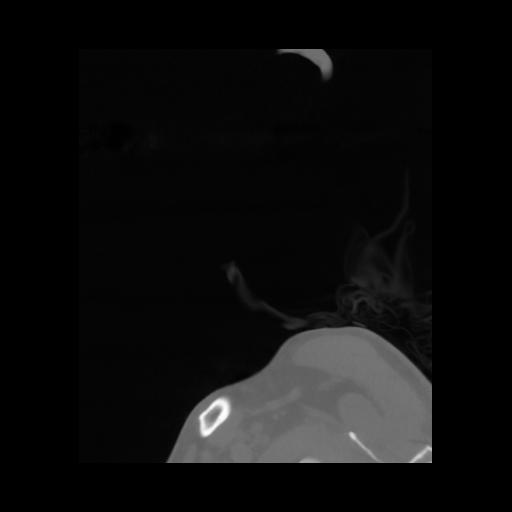

14 P.BLANDAS,,Sagittal,2.000,P.BLANDAS,Sagittal,